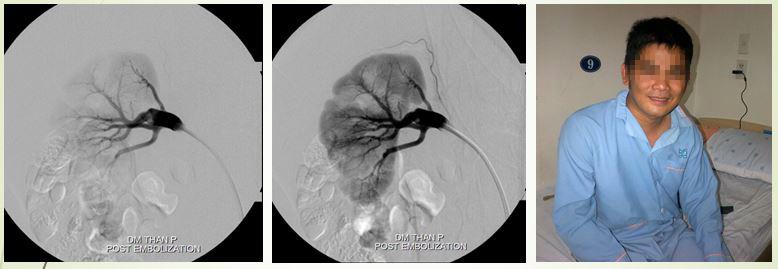

Hình ảnh DSA cho thấy có một vị trí thông động tĩnh mạch, làm cho lưu lượng tưới máu đến nhu mô thận giảm đáng kể, từ đó có thể giải thích tại sao bệnh nhân tăng huyết áp dù tuổi còn trẻ Kết quả siêu âm bụng tổng quát không ghi nhận bất thường, siêu âm động mạch thận: Nghi ngờ rò động mạch thận. Xét nghiệm máu trong giới hạn bình thường. Bác sĩ chẩn đoán: tăng huyết áp người trẻ – rò động tĩnh mạch thận. Câu hỏi đặt ra cho các bác sĩ là phải làm gì? Nếu can thiệp không thành công thì phẫu thuật, nhưng năm 2006 phẫu thuật thận cũng rất khó khăn. Các bác sĩ quyết định cố gắng can thiệp nội mạch, dùng keo, dùng bóng, dùng tất cả phương tiện có trong tay lúc đó, cuối cùng đã bít được chỗ thông nối động mạch thận và tĩnh mạch chủ.

Sau can thiệp, huyết áp bệnh nhân trở về bình thường, hết sức vui vẻ vì không cần uống thuốc hạ huyết áp nữa, và chi phí phải thanh toán cho ca can thiệp cũng rất thấp.

Ca lâm sàng thứ 2 là một bệnh nhân nam 63 tuổi, vào viện vì đau bụng, tiểu máu từng đợt… trước đó, ông đã đi khám từ Bắc chí Nam mà không nơi nào tìm ra hướng giải quyết cho tình trạng của mình. Tại bệnh viện, các bác sĩ đã tìm thấy nguyên nhân là bệnh nhân có rò động tĩnh mạch thận lưu lượng rất cao. Để khắc phục tình trạng này, BS Trần Chí Cường đã can thiệp, dùng bóng để giảm dòng chảy vào động mạch thận để có đường vào sâu hơn, bơm keo gây tắc vị trí thông động tĩnh mạch.

Kỹ thuật dùng bóng kiểm soát dòng chảy và bơm keo

Sau gây tắc bằng keo và bóng

Chỉ trong 24 giờ sau can thiệp, nước tiểu của bệnh nhân trong vắt, trở lại cuộc sống bình thường.